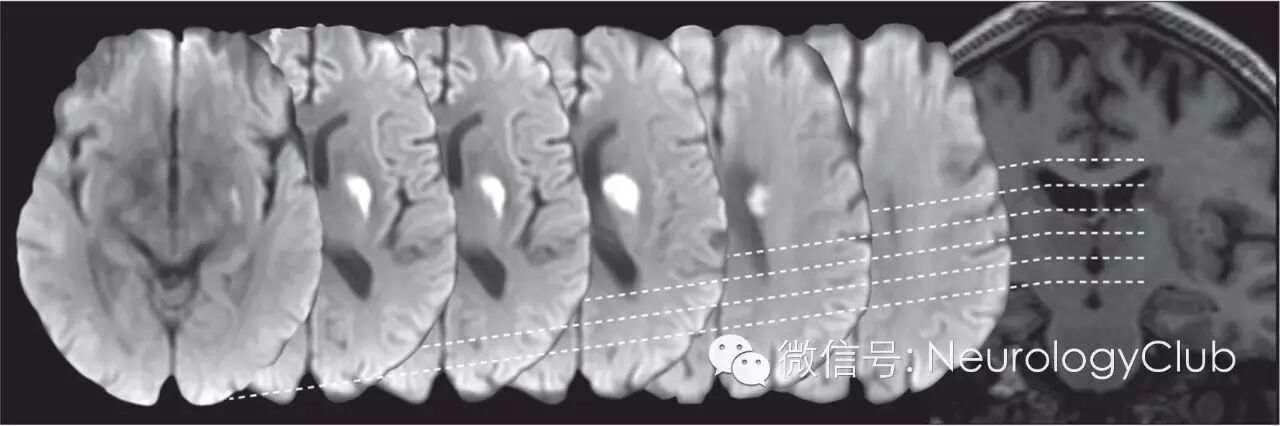

(DWI和T1WI示急性小梗死。从左至右为DWI上基底节区至半卵圆中心的连续层面;最右图为T1WI。冠状位T1WI上小梗死呈管状,沿穿支动脉走形

(T1WI[左]和DWI[右]上的连续层面的左侧基底节区新发小梗死。白线标注了冠状位上病灶的尺寸,在横断面上病灶近圆形,而冠状位上呈管状)

(DWI和FLAIR上不同部位形状的急性小梗死。A:内囊后肢小的卵圆形梗死;B:半卵圆中心小圆形梗死,伴白质高信号;C:内囊后肢稍大的卵圆形梗死,可见其他腔隙;D:外囊至半卵圆中心的管状梗死)